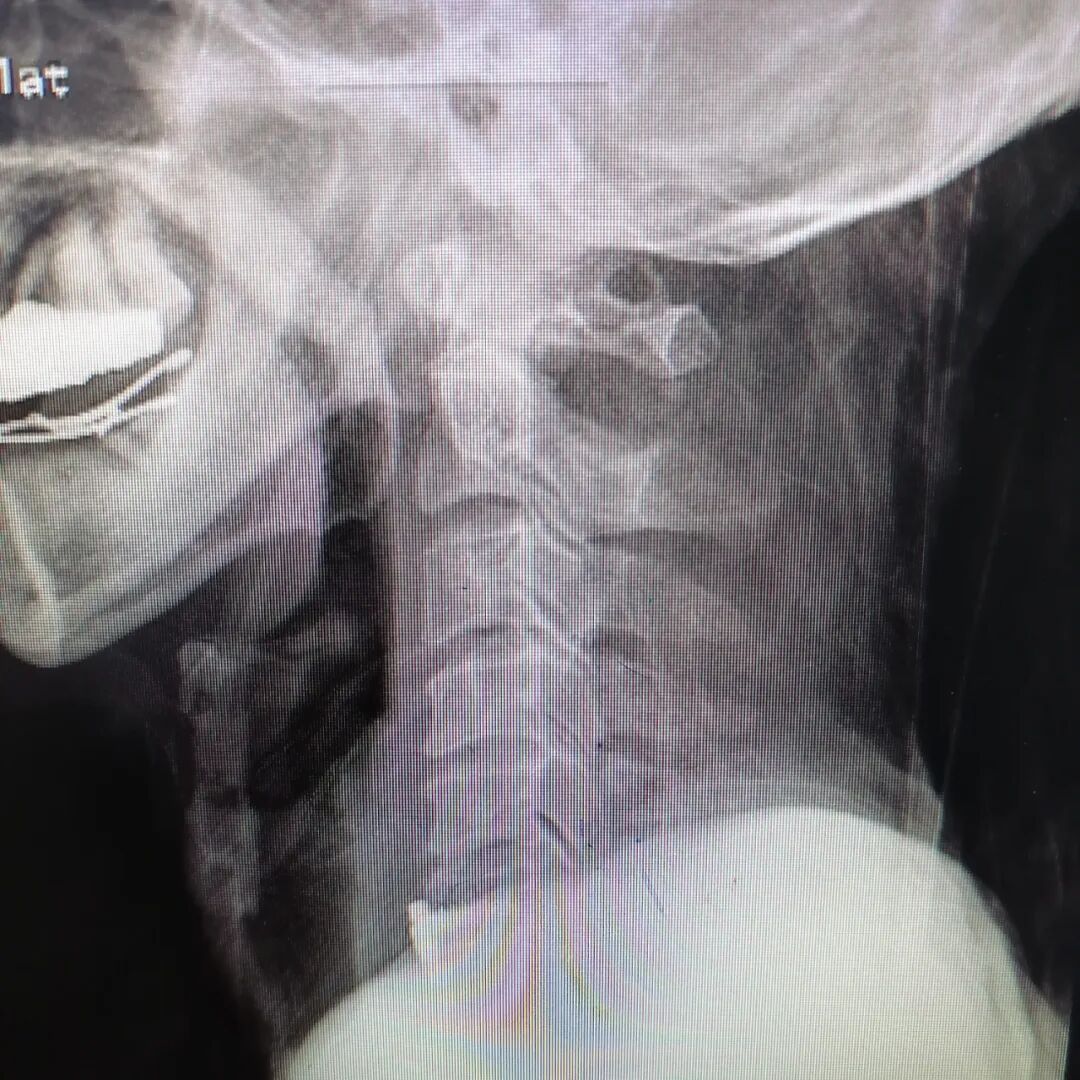

该患者为60岁老年男性,因“车祸伤后颈部疼痛并肢体活动障碍1小时余入院。”急诊CT显示:患者下颈椎严重骨折并脱位;入院查体显示:双上肢肌力3级(正常为5级),双下肢肢体肌力0级,四肢浅感觉减退,痛觉过敏,双膝、跟腱反射消失。

手术前

手术后

为尽快救治该患者,脊柱外科立即开通绿色通道,按照脊髓损伤给予药物治疗同时,严格颈部制动、轴线翻身,协调放射科、超声科等相关科室,减少患者搬动次数,尽快完善相关检查,避免损伤加重。MR结果显示颈部脊髓严重受损,排除手术禁忌后,脊柱外科况光荣主任团队全面研究患者骨折及脱位情况,充分讨论病情,分析手术难点后,决定行颅骨牵引复位+颈椎前路减压固定融合术。患者术后肢体活动明显改善:双上肢肌力恢复至4级+,左下肢肌力恢复至4级,右下肢肌力恢复至2级,复查影像学显示复位固定满意,脊髓减压效果良好。患者住院70天后康复出院,出院时可自行行走。